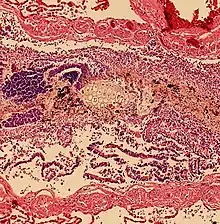

Pulmonary aspiration of acidic material (such as stomach acid) may produce an immediate primary injury caused by the chemical reaction of acid with lung parenchyma, and a later secondary injury as a result of the subsequent inflammatory response.[2]